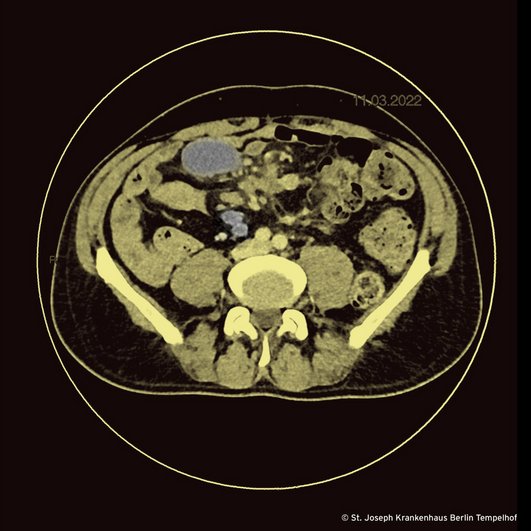

Eineinhalb Monate später – er hat immer noch keine HIV-Medikamente – kommt er ins St. Joseph Krankenhaus mit denselben Beschwerden. Er fühlt sich abgeschlagen, fiebert und verliert weiter an Gewicht. Wir sind uns sicher, es besser zu können. Wir veranlassen eine CT »von Hacke bis Nacke« und warten, wie vor dem Weihnachtsbaum sitzend auf die Röntgendemo. Herr Trübenbach, der Chef unserer Radiologie stellt uns die Bilder mit den Worten vor: »Was auch immer Sie getan haben, Sie haben es gut getan: Die Läsionen in der Lunge sind verschwunden. Im Abdomen sieht es allerdings schlecht aus.« Er zeigt uns viele eingeschmolzene mesenteriale Lymphknoten, von denen wir drei für Sie im Bild farblich gekennzeichnet haben. So weit so gut. Was soll es denn sonst sein? Wir punktieren einen der Lymphknoten und die Mikrobiologin sieht mikroskopisch säurefeste Stäbchen. Über die PCR erfolgt der Nachweis von Mycobacterium tuberculosis-Komplex. Molekularbiologisch finden sich keine Hinweise auf Resistenzen gegen Rifampicin und Isoniazid. Die Kulturen aus der Lungenklinik sind immer noch ohne Wachstum ebenso wie die – noch kurz bebrüteten – Kulturen aus dem Lymphknoten.